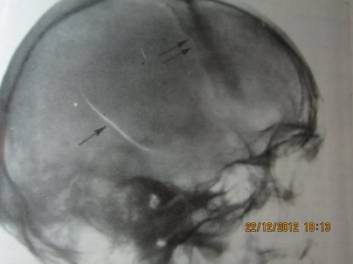

задней черепной ямки. Во всех 4-х группах. Это объясняется тем, что при ударно - волновом и механическом

воздействии вследствие передачи костям

черепа кинетической энергии формируется гидродинамический удар, действующий на

структуры голоного мозга и внутреннего уха (прямо и опосредовано). (cм Рисунок 1-4)

Рисунок 2